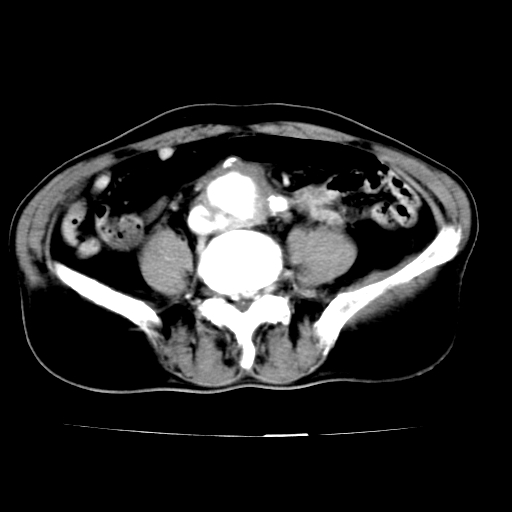

男,75岁,腹痛月余,彩超发现脐周腹主动脉异常回声。临床诊断:腹主动脉瘤。

ct诊断:右骼总动脉囊性动脉瘤并瘤内附壁血栓形成,与下腔静脉之间形成动静脉瘘。

请问各位老师:能排除动脉瘤破裂的可能吗?

各位老师注意到下腔静脉的充盈缺损了吗?注意到动静脉漏了吗?

当时是扫描的标准动脉期,可是下腔静脉与腹主动脉同步强化且幅度一致。所以我想动静脉瘘是存在的。